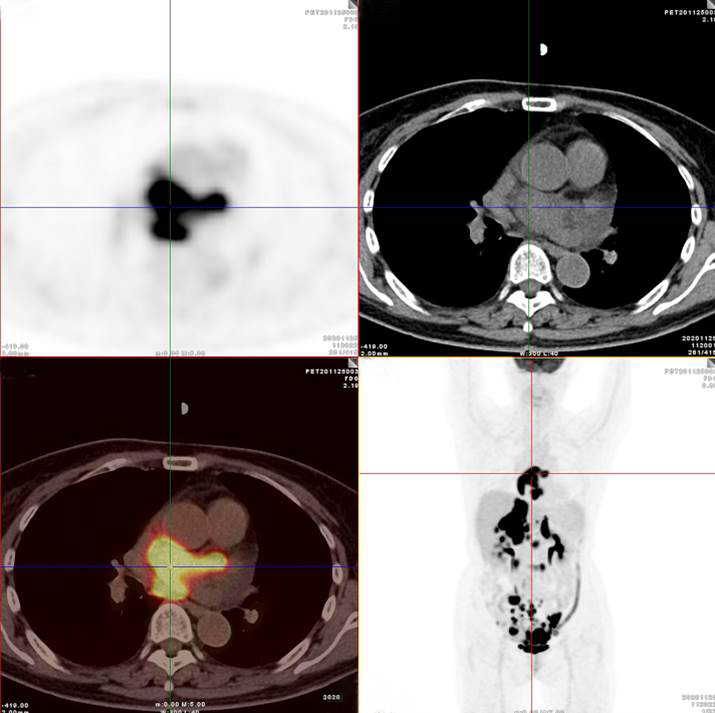

左/右心房病灶放射性攝取明顯增高